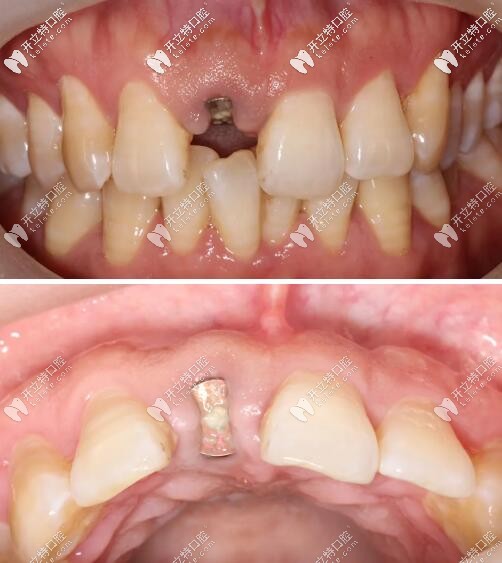

術(shù)后三個(gè)月復(fù)查見近遠(yuǎn)中齦乳頭高度維持良好,唇側(cè)較豐滿。

門牙外傷即刻種植牙三個(gè)月后